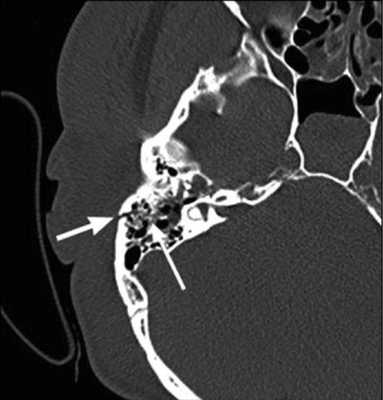

Рис. 1. КТ височных костей пациентки М. а — коронарная проекция: деструктивная полость в пирамиде височной кости, заполненная субстратом неоднородной плотности, капсула лабиринта значительно разрушена на уровне базального и апикального завитков улитки, латерального и верхнего полукружных каналов; б — аксиальная проекция: деструктивная полость с разрушением задней грани пирамиды, передневерхней и нижней поверхности.

По результатам МРТ головного мозга правая пирамида височной кости деформирована, увеличена в объеме, выполнена субстратом размером до 5,5—2,8—3 см, распространяющимся на область внутреннего слухового прохода, заднего полукружного канала, медиальные отделы барабанной полости, сосцевидный отросток. Описанный субстрат изо-гипоинтенсивен в режиме Т1, гиперинтенсивен — в Т2 и non-EPI DWI (рис. 2). Заключение: признаки рецидива холестеатомы с деструктивными изменениями структур внутреннего и среднего уха на фоне хронических воспалительных изменений.

Рис. 2. Магнитно-резонансная томография головного мозга пациентки М. Деформированная, увеличенная в объеме пирамида височной кости выполнена мягкотканым субстратом.